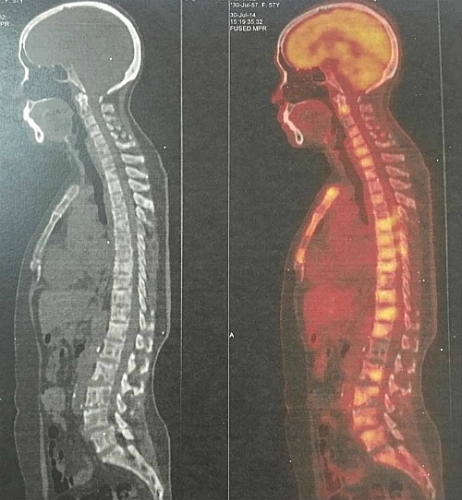

Dấu hiệu nhận biết ung thư di căn cột sống

Ung thư di căn cột sống là gì? Dấu hiệu nhận biết ung thư di căn cột sống? Điều trị ung thư di căn cột sống như thế nào?...là thắc mắc của nhiều bệnh nhân.